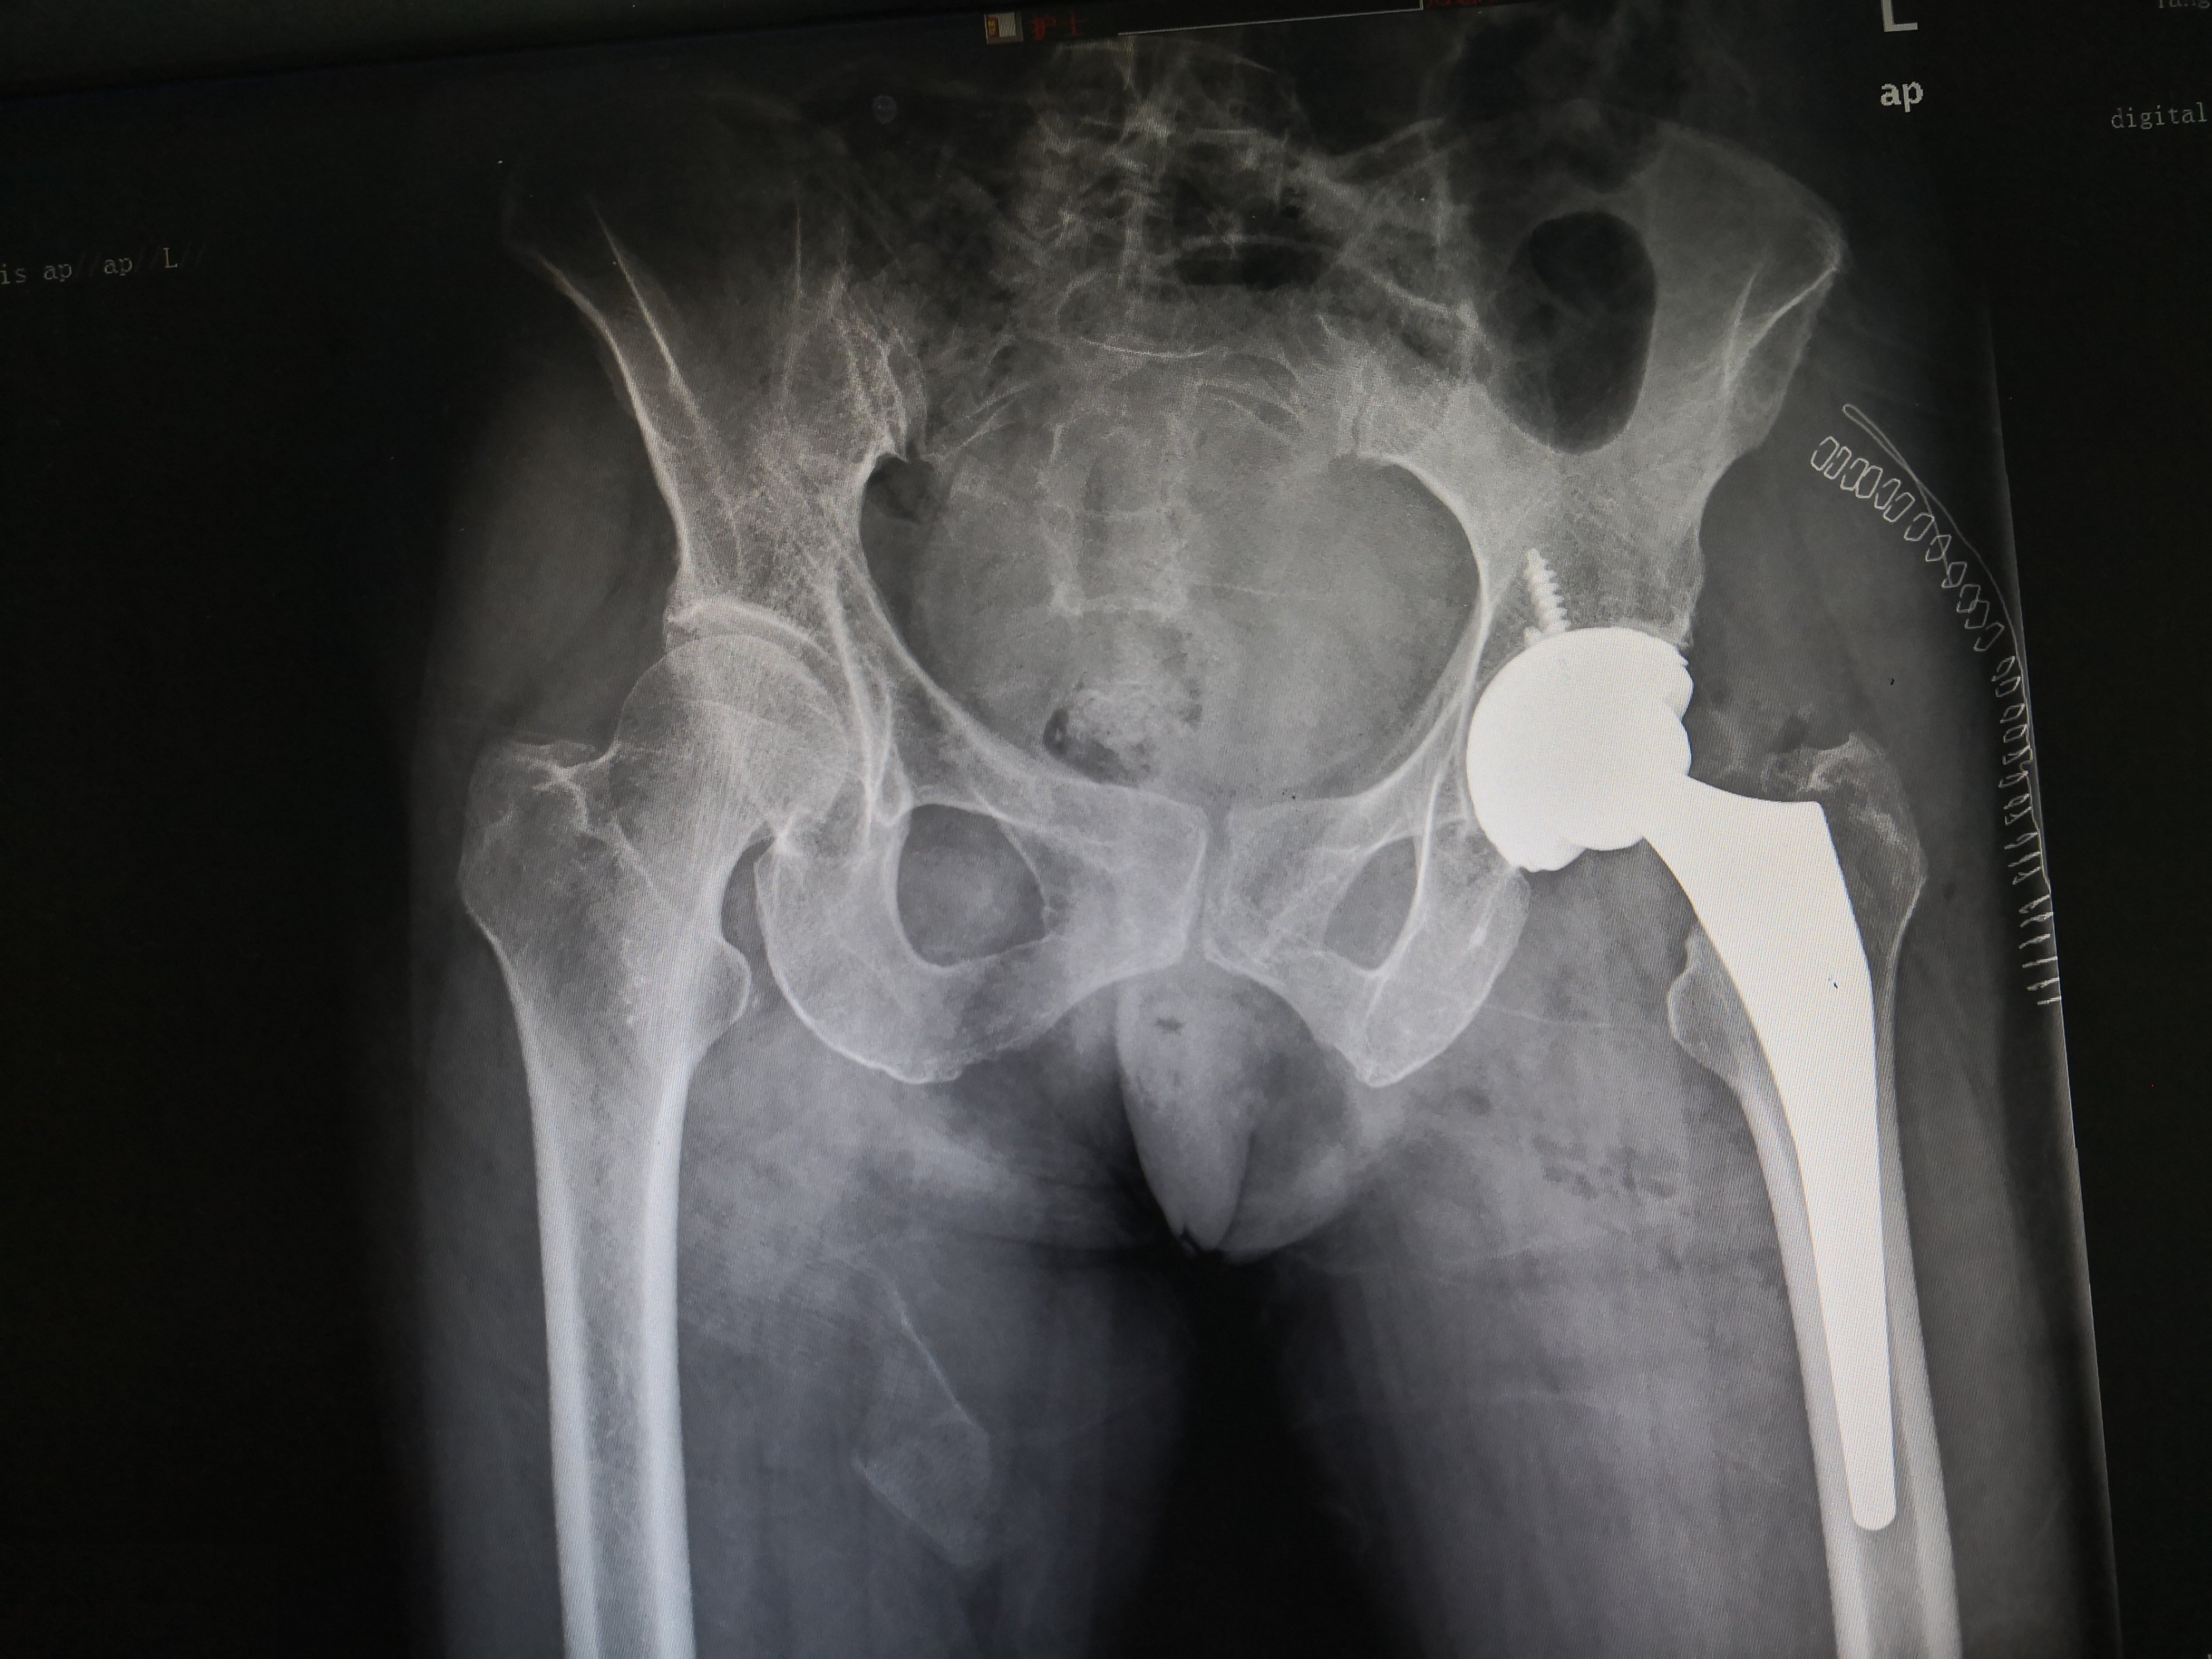

术后人工全髋关节

IMG_20190323_184730.jpg